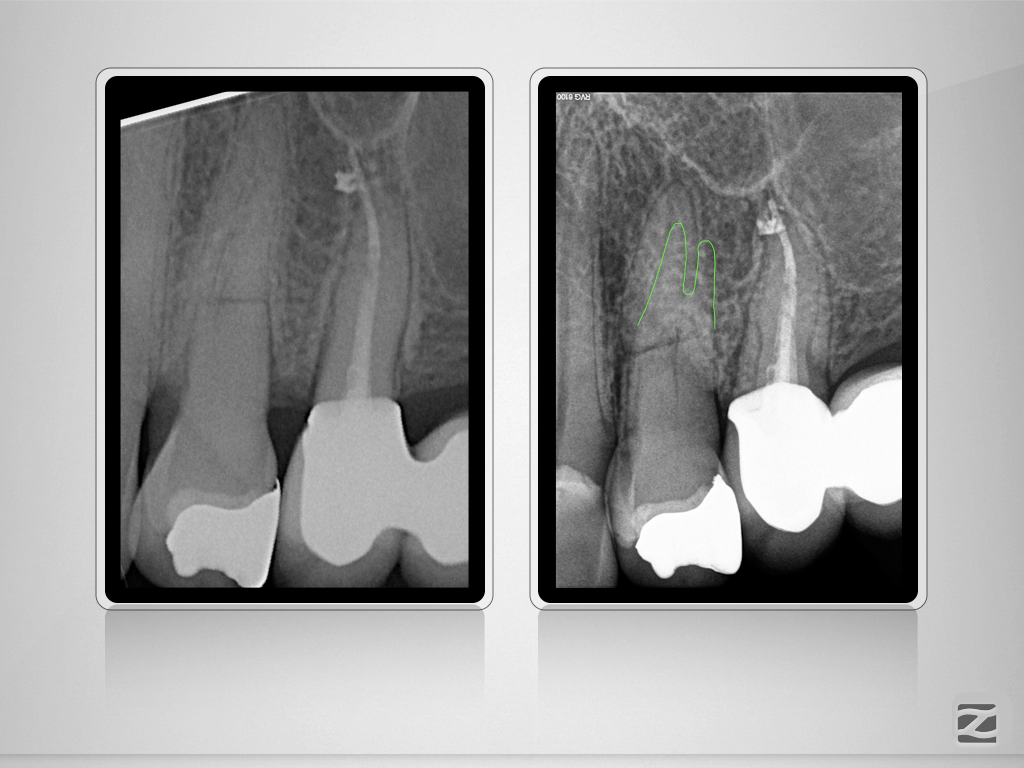

24D.006

Und nun? Die Auflösung.